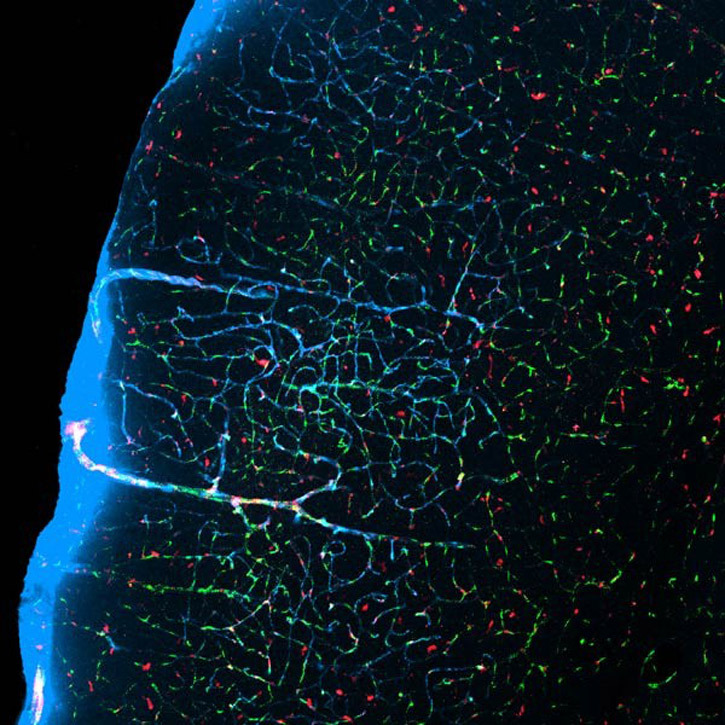

Photo: Courtesy of Uppsala Universitet. Nerve Cells and Glial Cells.

Researchers led by Maiken Nedergaard at the University of Rochester Medical Center have discovered a “need” for sleep. The team of researchers used a technique, called two photon microscopy, to examine the brains of sleeping mice by injecting red and green dyes and examining how they flowed through the brain.

Photo: Courtesy of Maiken Nedergaard/Jeff Iliff. When asleep, spaces between neurons (light blue) flush out waste.

The study showed that the glymphatic system cleans cerebrospinal fluid around glial cells (brain cells), flushing out protein waste from spaces between neurons in a “scrubbing” process. This waste has been found to have associations with Alzheimer’s disease.

The researchers discovered that during sleep brain cells contract, increasing the space between the cells by as much as 60 percent, allowing the spinal fluid to wash more freely through the brain tissue. The scientists found that the glymphatic system was almost 10 times more active during sleep than when awake.